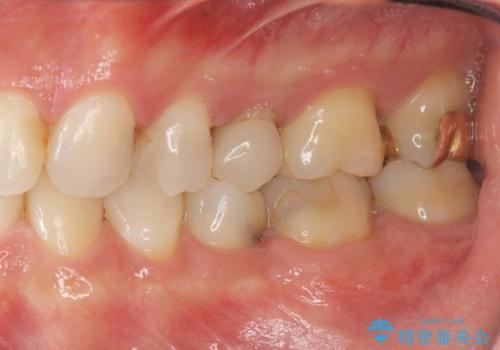

- 虫歯の全体的な検査を求めて来院されました。

X線検査を行なったところ、以前他院にて治療した白い詰め物の下に虫歯の再発を認めました。